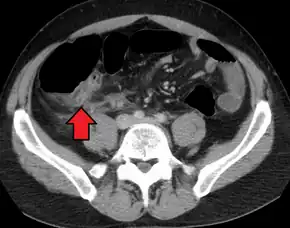

Computed tomography

Where it is readily available, computed tomography (CT) has become frequently used, especially in people whose diagnosis is not obvious on history and physical examination. Although some concerns about interpretation are identified, a 2019 Cochrane review found that sensitivity and specificity of CT for the diagnosis of acute appendicitis in adults was high.[59] Concerns about radiation tend to limit use of CT in pregnant women and children, especially with the increasingly widespread usage of MRI.[60][61]

The accurate diagnosis of appendicitis is multi-tiered, with the size of the appendix having the strongest positive predictive value, while indirect features can either increase or decrease sensitivity and specificity. A size of over 6 mm is both 95% sensitive and specific for appendicitis.[62]

However, because the appendix can be filled with fecal material, causing intraluminal distention, this criterion has shown limited utility in more recent meta-analyses.[63] This is as opposed to ultrasound, in which the wall of the appendix can be more easily distinguished from intraluminal feces. In such scenarios, ancillary features such as increased wall enhancement as compared to adjacent bowel and inflammation of the surrounding fat, or fat stranding, can be supportive of the diagnosis. However, their absence does not preclude it. In severe cases with perforation, an adjacent phlegmon or abscess can be seen. Dense fluid layering in the pelvis can also result, related to either pus or enteric spillage. When patients are thin or younger, the relative absence of fat can make the appendix and surrounding fat stranding difficult to see.[63]